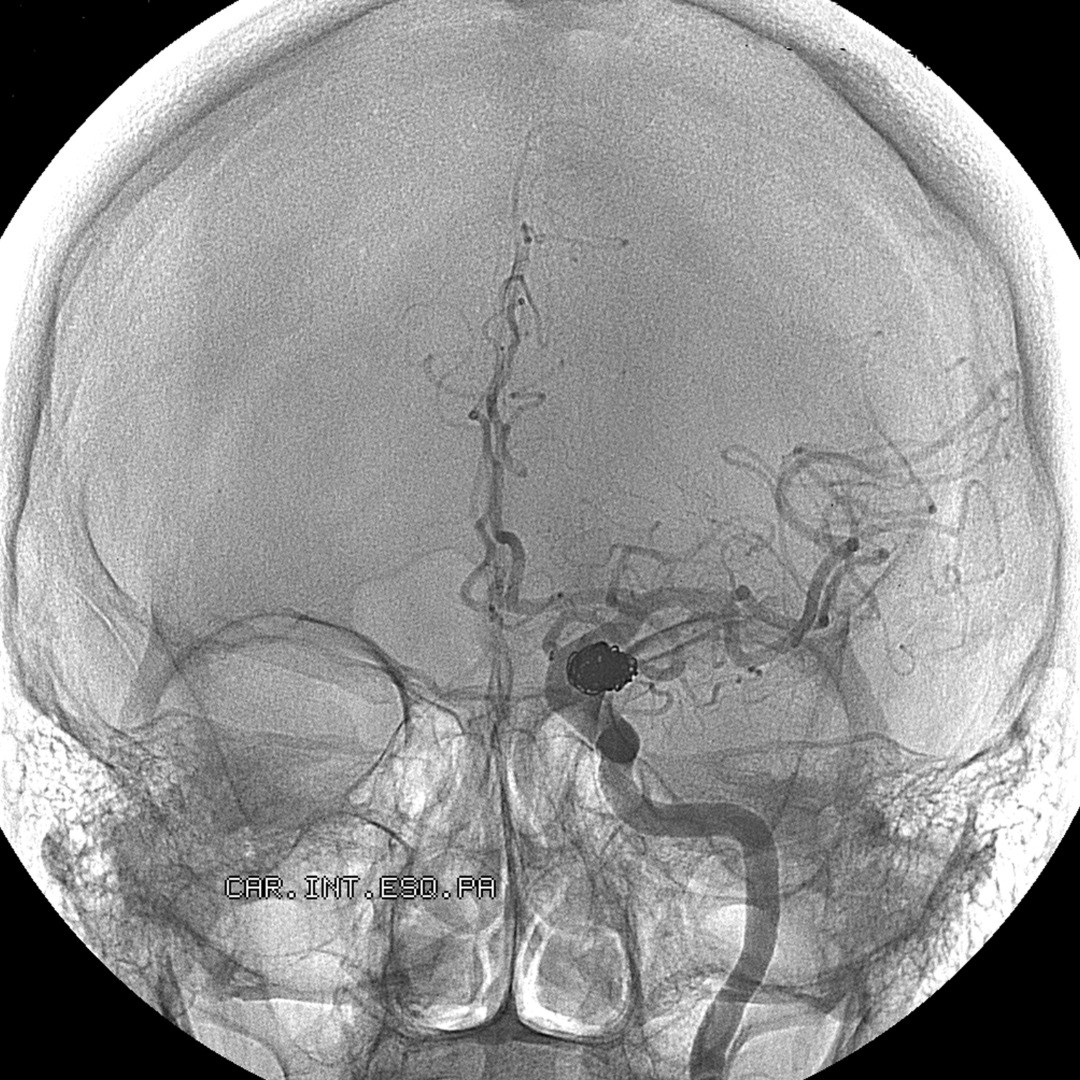

Typically, a catheter is inserted via a small incision and guided through the arteries to the area of interest. The catheter can then be used to deliver drugs, diagnostic aids such as dyes, coils, embolic materials or restorative equipment such as vascular stents.

Expertise in neuroendovascular procedures is an important tool in addressing a significant number of issues that patients experience. Our highly skilled cerebrovascular and endovascular surgeons employ sophisticated neurosurgical techniques to diagnose and treat both common and complex brain and spine disorders, procedures such as:

- Cerebral aneurysm coiling and surgical clipping

- Embolization for brain arteriovenous malformations (AVMs)